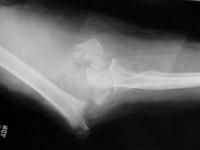

Click for larger image

Finally, the titanium olecranon screw was replaced with a longer 6.5 mm stainless screw and tension band wire. Following this, the elbow was stabilized with an EBI hinged external fixator (not shown), planning to leave this on four weeks, anticipating inadvertent weight bearing due to the patient's bilateral calcaneal fractures.